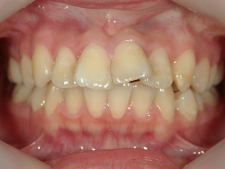

no.6_8296_治療前_右.jpgno.6_8296_治療前_正面.jpgno.6_8296_治療前_左.jpg

矯正歯科 治療後

no.6_8296_治療後_右.jpgno.6_8296_治療後_正面.jpgno.6_8296_治療後_左.jpg